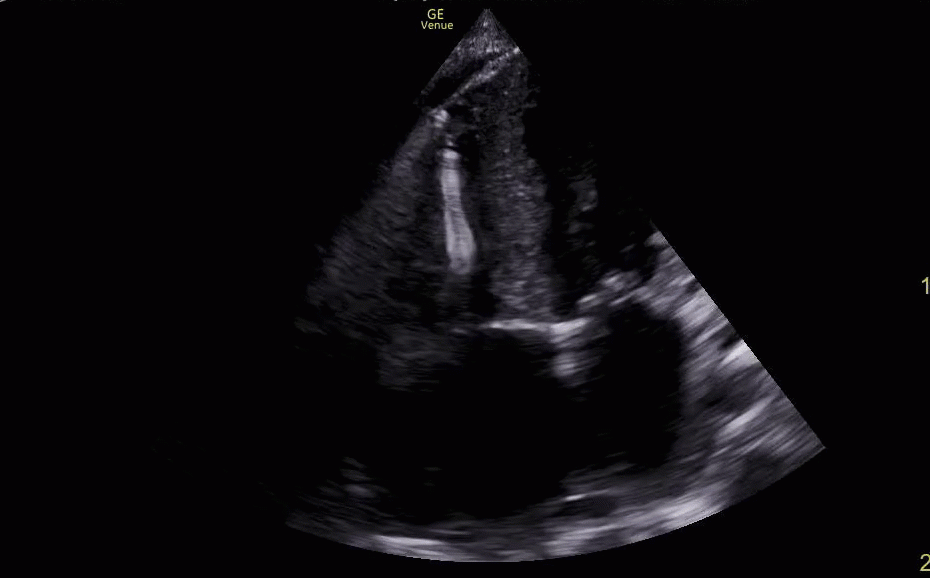

Pericardial and Pleural Effusions

Pericardial Effusion

Pacer Lead Migration

Mitral Valve Prolapse

Left Atrial Mass

Complete Heart Block

Atrial Flutter

Supine vs Left Lateral Decubitus

Normal 4 View Echo